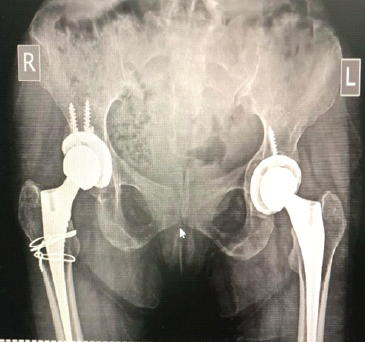

Wheelchair to Walking: Quadruple Arthroplasty of Hip and Knee Joints in a Patient with Severe Ankylosing Spondylitis

Remington C. Crossnoe , Varun M. Trivedi , Sterling J. DeShazo , Reagan L. Crossnoe ………………………………p.227-232